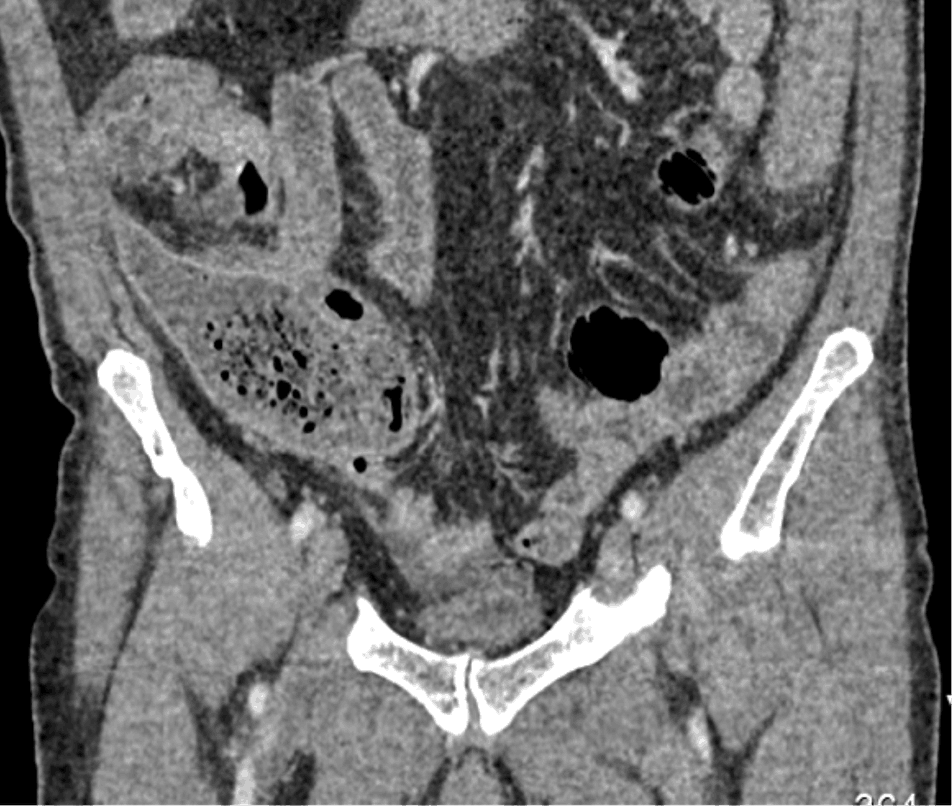

Особая категория инородных тел в организме человекам – это инородные тела, оставленные в результате хирургических вмешательств. Это относительно редкое осложнение. До 50% всех инородных тел составляют забытые хирургические тампоны, марлевые салфетки дренажные трубки, фрагменты катетеров, хирургические инструменты. Чаще всего инородные тела остаются после полостных операций, реже – после лапароскопических, эндоскопических, чрескожных. Наиболее распространенными локализациями ИТ являются брюшная полость, полость таза, также описаны случаи их нахождения в грудной, плевральной, перикардиальной полостях, забрюшинном пространстве, полости черепа, мягких тканях.

Госсипибома – это инородное тело тканевого происхождения, случайно оставленное в операционной ране: грудной, брюшной полости, малом тазу, забрюшинной клетчатке, мягких тканях и др. Клиническая картина зависит от расположения инородного объекта и вызванных им осложнений.

Позволяет достоверно выявить инородное тело в анатомически сложной области, оценить степень изменений в окружающих тканях, взаимоотношение инородного тела с прилежащими органами, а также выявить наличие возможных осложнений.

Метод выбора для выявления госсипибомы - КТ. В раннем послеоперационном периоде госсипибома наиболее достоверно диагностируется при визуализации округлого образования с губчатой внутренней структурой, с множественными пузырьками газа в структуре. При в/в контрастировании визуализируется тонкое периферическое кольцо контрастного усиления, соответствующее гранулематозному воспалению вокруг инородного тела. В позднем послеоперационном периоде госсипибома может утратить губчатую структуру и КТ-картина может быть сходна с ограниченным скоплением жидкости или с абсцессом. В отдаленном послеоперационном периоде госсипибому следует дифференцировать с новообразованиями, при этом отмечается отсутствие достоверного накопления контрастного вещества как в центральной зоне, так и стенке госсипибомы. В позднем и отдалённом постоперационном периоде также возможна кальцификация стенок госсипибомы.